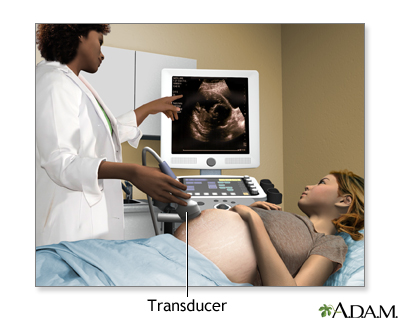

A pregnancy ultrasound is an imaging test that uses sound waves to create a picture of how a baby is developing in the womb (uterus). It is also used to check the female pelvic organs during pregnancy.

How the Test is Performed

To have the procedure:

- You will lie on your back on an exam table.

- The person performing the test will spread a clear, water-based gel on your belly and pelvis area. A handheld probe will then be moved over the area. The gel helps the probe transmit sound waves.

- These waves bounce off the body structures, including the developing baby, to create a picture on the ultrasound machine.

In some cases, a pregnancy ultrasound may be done by placing the probe into the vagina. This is more likely in early pregnancy. Many women will have the length of their cervix measured by vaginal ultrasonography around 20 to 24 weeks of pregnancy.